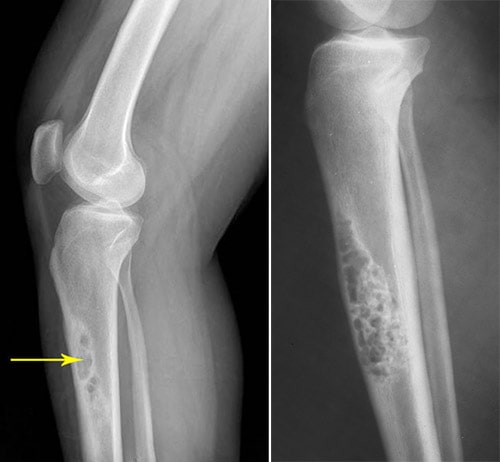

Intracortical Osteosarcoma

General Information Intracortical osteosarcoma is an extremely rare type of osteosarcoma that arises within and is usually confined to the cortex of the bone. It is a high grade osteosarcoma that is confined to the cortex of a long bone Intracortical osteosarcoma is...